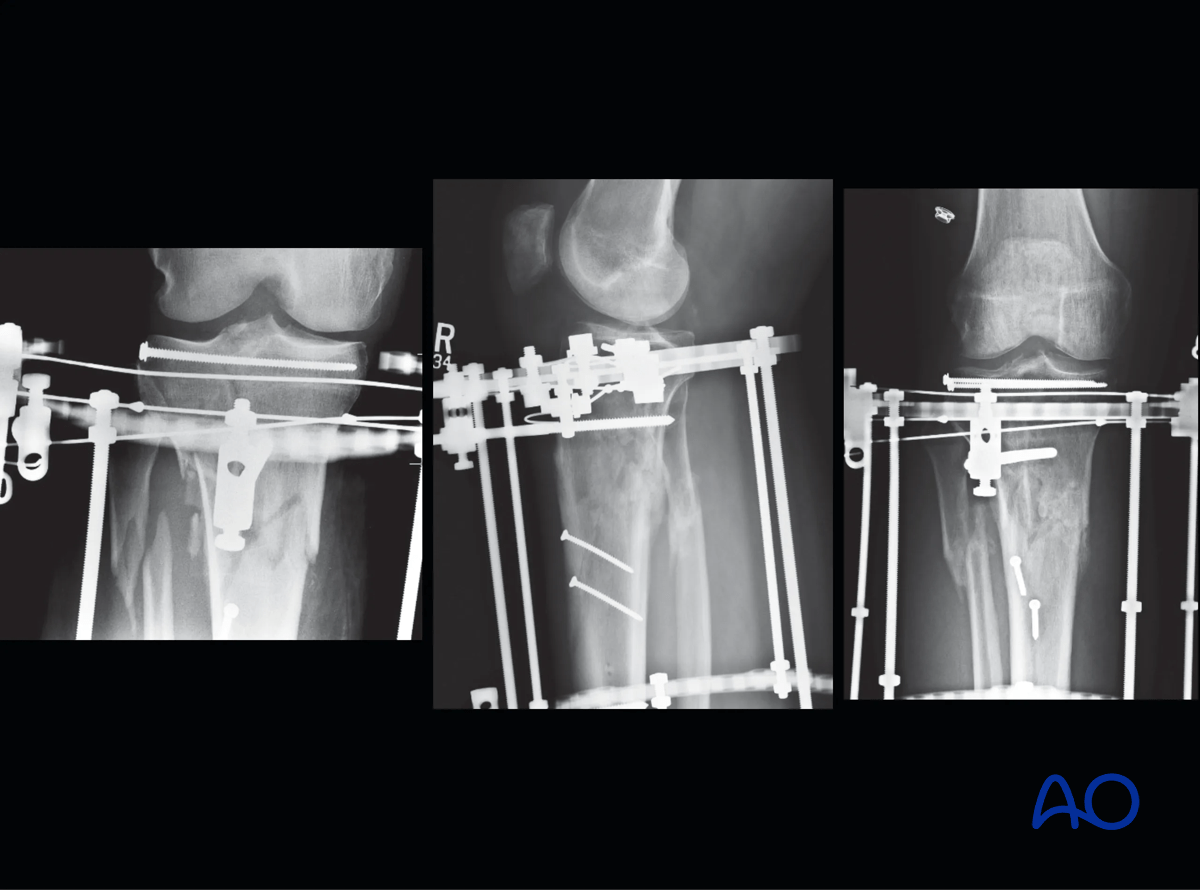

9. Case example

The clinical case shows a 45-year-old man injured in a motorcycle accident, sustaining a closed injury of his proximal tibia of the type 41.C2.2. Initial treatment consisted of placement of a temporary spanning frame and CT scanning for preoperative planning. Forty-eight hours later definitive fixation was performed.

Proximal tibia fracture – a closed injury of the type 41.C2.2

The articular surface was reduced percutaneously with a clamp and then stabilized with a 3.5 mm lag screw positioned close to the joint to leave room for olive wires for the ring fixator. The bone fragment containing the tibial tubercle was also fixed to the intact shaft with two 3.5 mm lag screws.

Proximal tibia fracture – ring fixation: reduction of articular surface

A three-ring frame was assembled using two full rings in the diaphysis and a 5/8 ring at the joint. The diaphyseal fixation was two Schanz screws off each ring and three wires and one Schanz screw in the reassembled articular block. Two of the wires proximally were placed as opposing olive wires.

The patient was allowed immediate active and passive motion of the range of knee. At eight weeks the patient was allowed weight bearing.

Proximal tibia fracture – ring fixation: a three-ring frame

The frame was removed at 16 weeks after fracture healing.

Proximal tibia fracture – ring fixation: the frame was removed at 16 weeks after fracture healing